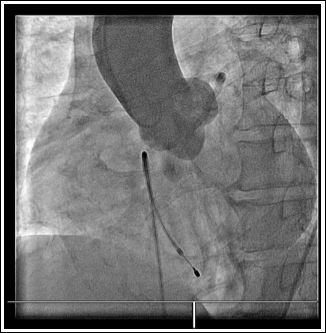

The fourth case was a 51-year-old male known to have hypertension who presented with post exertional syncope. His ECGs showed ST elevation in the inferior leads. He also developed complete heart block and haemodynamic instability. During emergency coronary angiography, multiple attempts to cannulate the Right Coronary Artery (RCA) in its expected location were unsuccessful. Left coronary angiogram with aortogram did not reveal any identifiable RCA origin (Figure 7). There was moderate to severe long segment of disease in the proximal LAD. The Left Circumflex (LCx) artery was a large calibre vessel with an occlusive stump at its distal bifurcation with an obtuse marginal branch (Figure 8). Following wiring of the occluded distal circumflex segment and balloon angioplasty with restoration of antegrade flow, it can then be seen that the Right Coronary Artery (RCA) actually arises from the distal LCx vessel (Figures 9 & 10). After PCI of the distal LCx lesion with a drug eluting stent, patient improved with resolution of bradycardia and hypotension. Patient subsequently made an uneventful recovery.

Figure 7: Aortogram without any contrast filling of the origin of right coronary artery in its expected location.